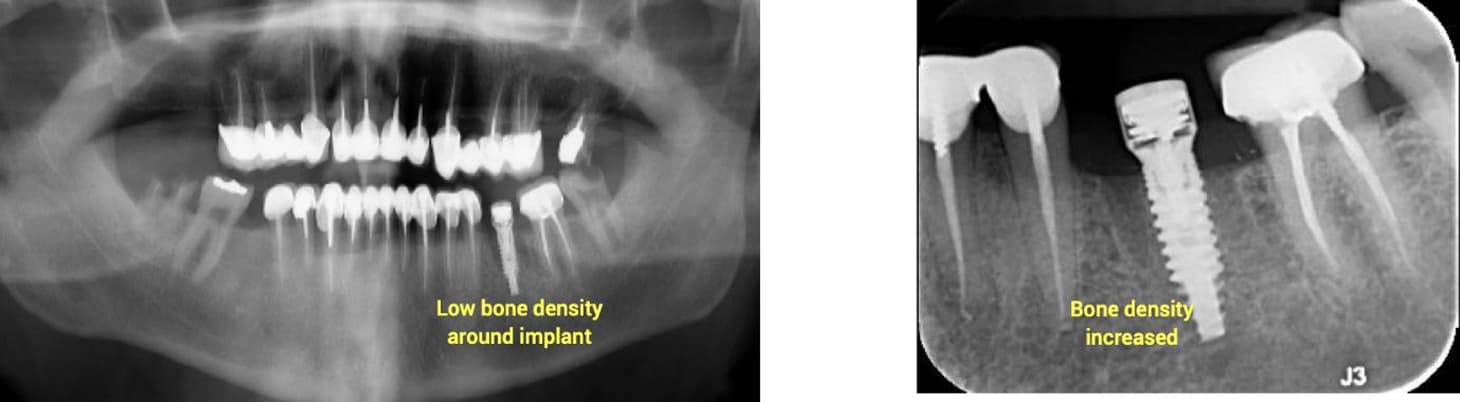

A 71-year-old healthy patient with poor bone quality presented following failure of a previous implant. A new implant was placed using a MED healing abutment to enhance the healing environment and promote bone regeneration. Radiographic evaluation at insertion revealed low bone density around the implant site.

After 60 days, radiographs demonstrated a marked increase in bone density surrounding the implant, indicating successful osseointegration and restoration of bone volume. The improved peri-implant bone quality enabled a stable impression and subsequent prosthetic rehabilitation, confirming the effectiveness of the MED healing abutment in supporting bone regeneration and implant stability in compromised sites.